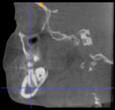

Three points determined the Acta plane: O, F right (FR), and F left (FL) (Table 2). Point O is the midpoint between the most craniodorsal point of the dorsum Sella and the most posterior dorsal point of the Basion in the midsagittal plane (Figure 1). Both points F are a result of the intersection between two lines: the line that connects the most inferior points of the lower orbital margins, right and left, and a line perpendicular to this line that runs through the most external points of the orbital margins, right and left (Figure 2). The new transverse reference plane, the Acta plane (Figure 2), is created by connecting the O-point (Figure 1) with FR and FL (Figure 2).

Figure 1.

Point O (green dot) is the midpoint between the dorsum Sella (Se) (red dot) and the Basion point (Ba) (yellow dot).

When determining the internal reference of the skull, the aim was to determine an origin point in the midsagittal plane, as previous studies have confirmed the consistency of the landmarks in the midsagittal plane [17,34]. At first, the midpoint between the left and right anterior clinoid processes was considered as the origin point. However, the left and right anterior clinoid processes have been reported as a reference with low reliability [35], and they were asymmetric in dry skulls as well as in many CBCT images from this sample. The second option was to use the most anterior border of the dorsum Sella. However, the Sella landmarks (Sella, Sella inferior, Sella posterior) are highly dependent on the DICOM orientation [17,35,36]. On the other hand, the most superior-posterior point of the dorsum Sella seemed more accessible and less orientation-dependent on the CBCT images. However, after using this point to align the CBCT scans, the final head position rolled too far backward. This issue was probably caused by the excessively high position of the dorsum Sella relative to the F-points. To address this discrepancy, the origin point was set in a lower position. One of the options considered was the Basion point. However, its position was too low in regard to the F points, which resulted in a forward-rolled skull after reorientation. As a result, the midpoint between the Basion and the dorsum Sella was adopted as the origin point, named point O.